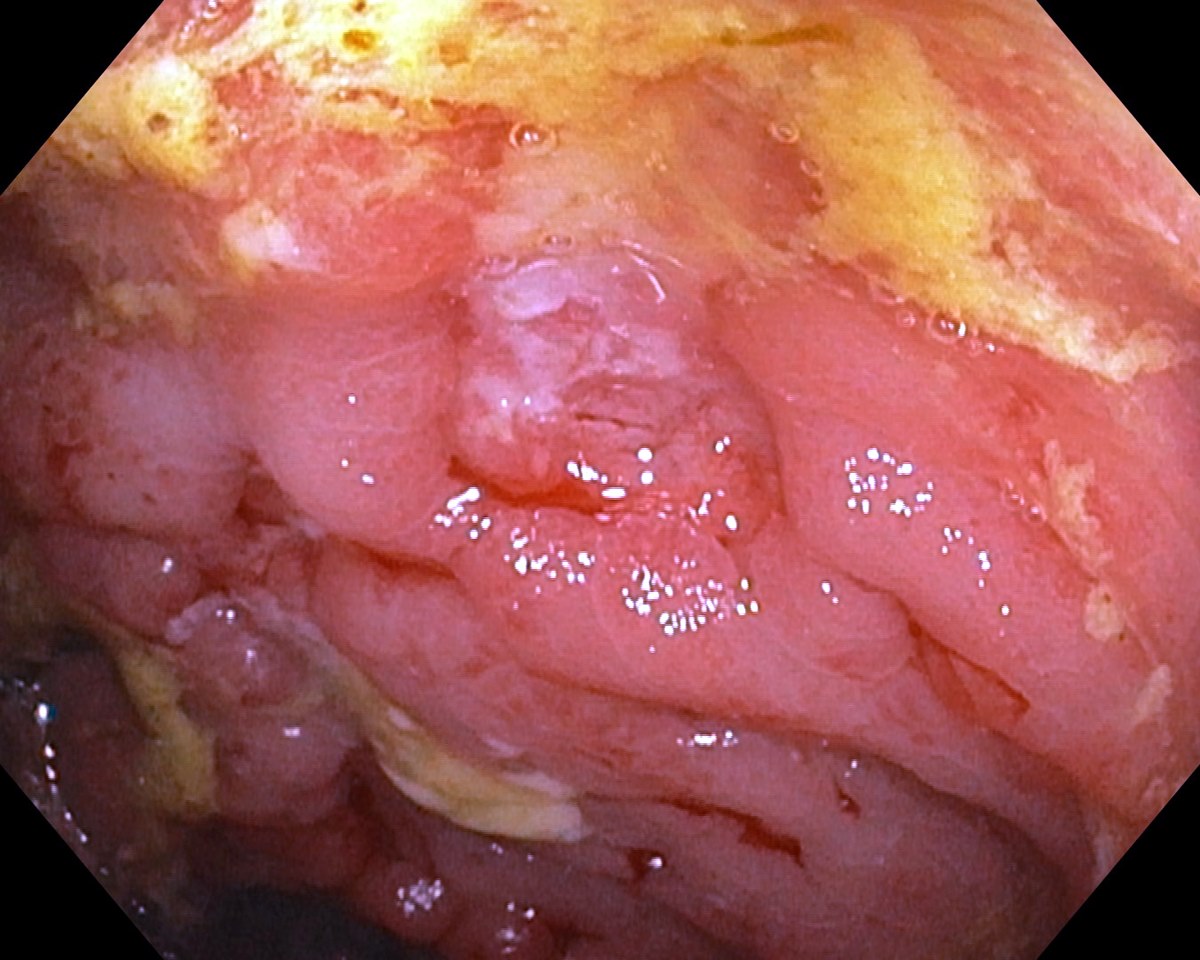

![]() Severe Rectal Crohns Disease  |

Severe Rectal Crohns Disease